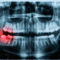

Missing Teeth: Gum disease is one of the leading causes of tooth loss in adults. Dental implants can be placed along with gum restoration/grafting procedures to restore your smile.